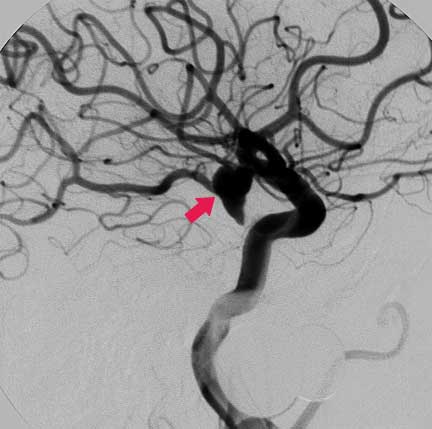

CASO 1 : Embolización endovascular de aneurismas con microespiras (coils) en paciente anciano y de alto riesgo para cirugía abierta

Angiografía antes de la embolización

Angiografía después de laembolización la cual muestra cierre completo del aneurisma